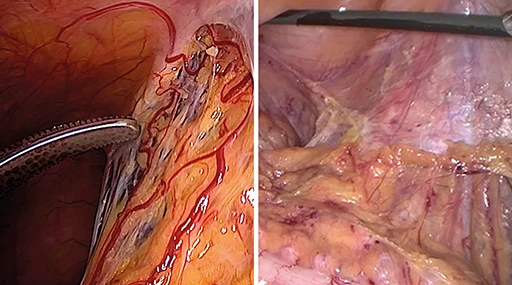

Miglioramento selettivo del colore (SCE)

Senza SCE

Le strutture e i vasi sono appena visibili.

Con SCE

Migliore visibilità delle strutture e delle imbarcazioni, aspetto naturale preservato.

Cambiamento di colore (CS1 / CS2)

Senza cambiamento di colore (CS1 / CS2)

Strutture e imbarcazioni sono appena visibili, molte sfumature di rosso.

Con Color Shift (CS1 / CS2)

Migliore visibilità delle strutture e dei vasi, riduzione delle sfumature di rosso, colori fortemente contrastati.